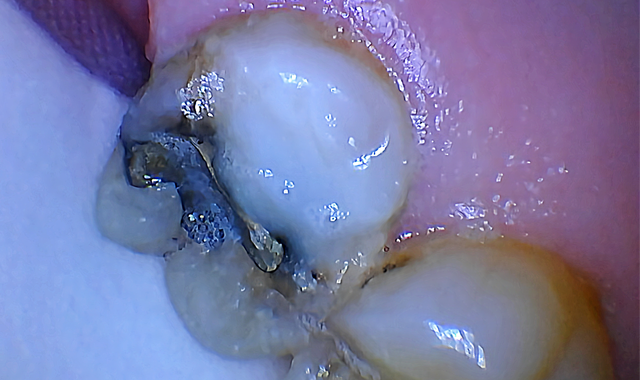

A pre-operative diagnostic radiograph showed no endodontic pathology. She is in excellent periodontal health (Fig. 1). Oral evaluation of the patient indicated that the palatal cusp of #15 fractured subgingivally to the level of the alveolar crest (Fig. 2).

Fig. 1 Fig. 2